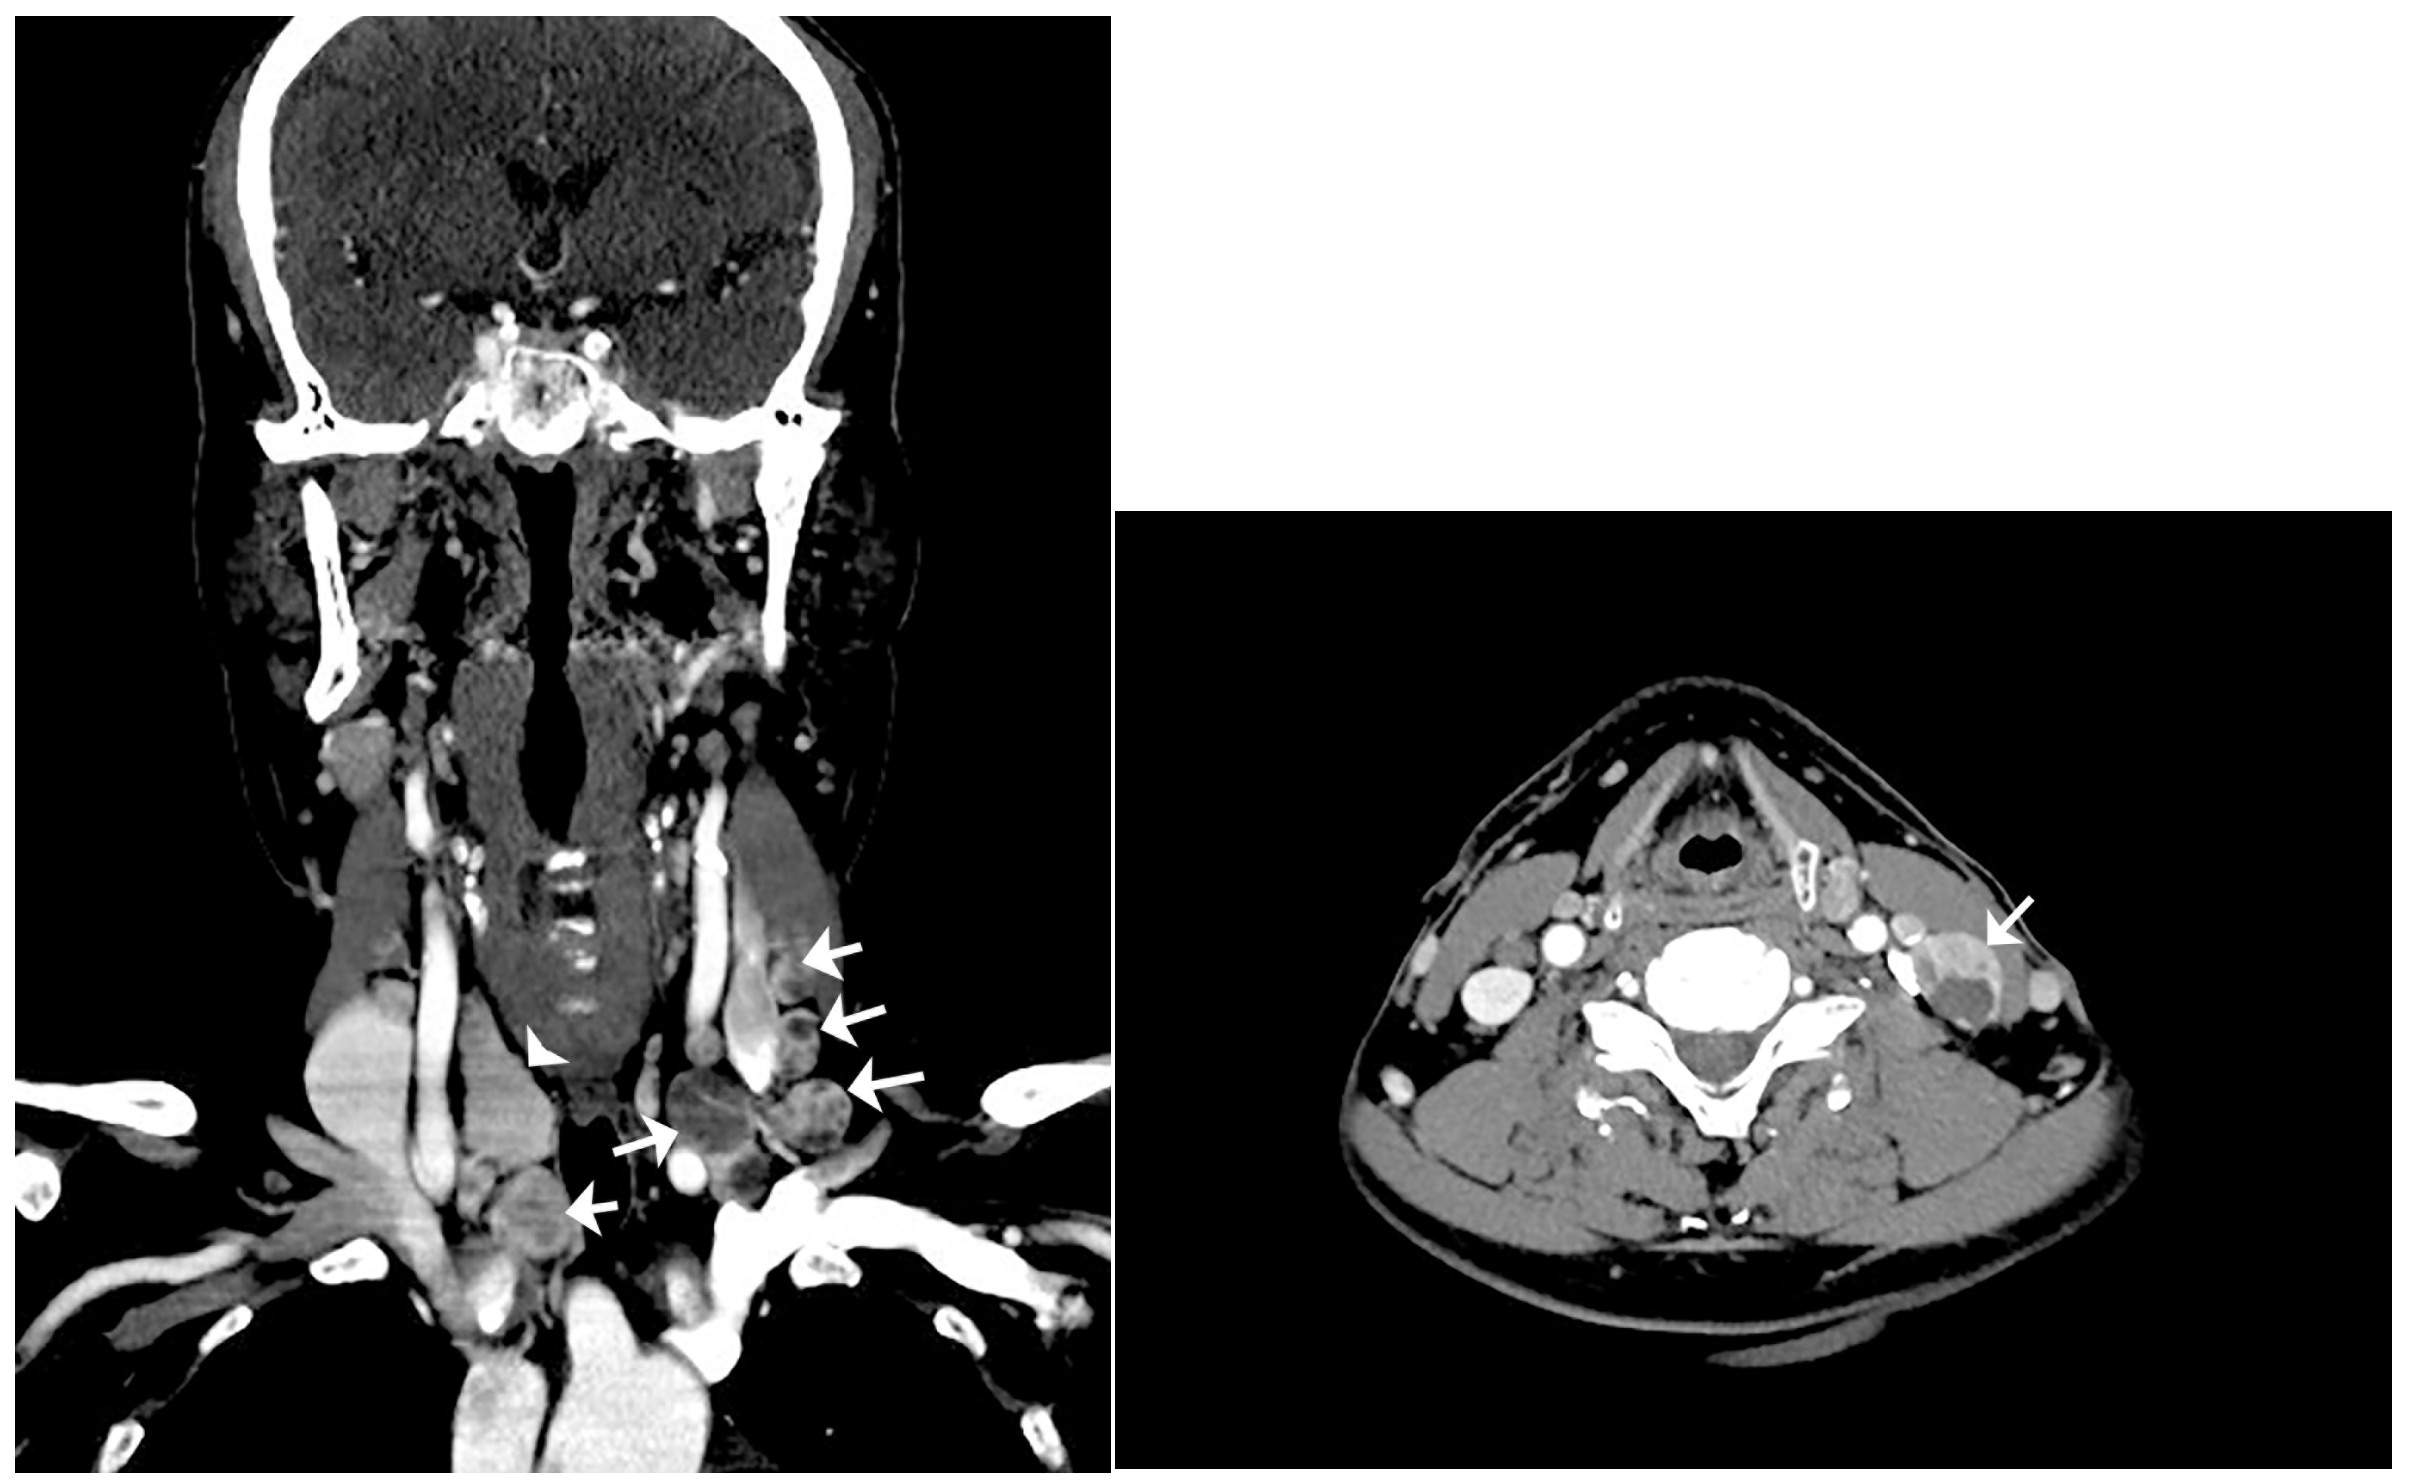

Kang, Y.-N.; Cha, J.-G. Benign Intranodal Thyroid Tissue Similar to Nodal Metastasis of Thyroid Papillary Carcinoma: A Rare Case Report. Diagnostics 2023, 13, 577. https://doi.org/10.3390/diagnostics13030577